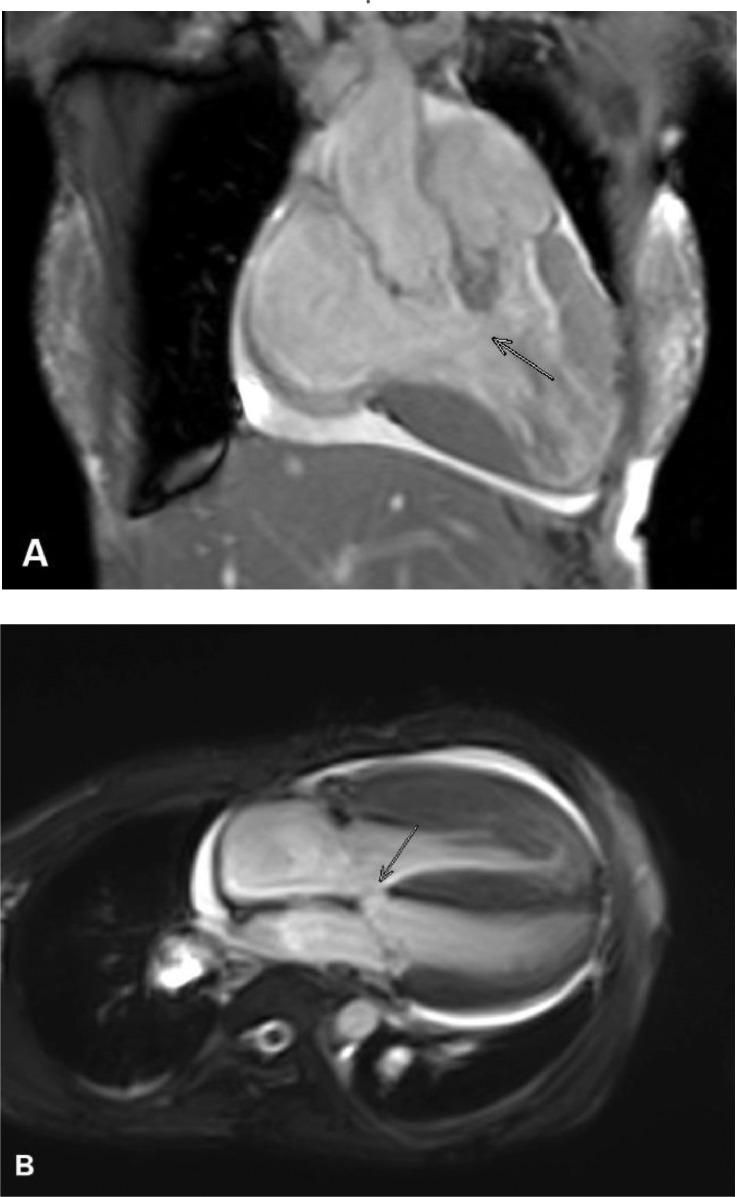

Double outlet right ventricle (DORV) is a congenital cardiac malformation that occurs in 1%-3% of individuals with congenital heart defects. Cardiac magnetic resonance imaging (MRI) may play an important role in the anatomy of the ventricular septal defect, functional status of both ventricles, and in identifying any residual stenosis or regurgitation or coexistent anomalies. Here, we present a case of a 28-years-old woman who came to our emergency department with shortness of breath. The patient felt shortness of breath on exertion and improved with rest. Clinical examination showed no abnormalities except low oxygen saturation of 65%. After echocardiography and cardiac MRI were done, it was concluded that she had a double outlet right ventricle with peri membranous ventricular septal defect (VSD), pulmonary hypertension, and pericardial effusion. This study highlights the role of cardiac MRI in assessing DORV.

右心室双出口(DORV)是一种先天性心脏畸形,在先天性心脏缺陷患者中发生率为1%-3%。心脏磁共振成像(MRI)在室间隔缺损的解剖结构、双心室功能状态以及识别任何残余狭窄或反流或并存异常方面可能发挥重要作用。在此,我们报告一例28岁女性患者,她因呼吸急促前来我院急诊科就诊。患者在运动时感到呼吸急促,休息后症状改善。临床检查除氧饱和度低至65%外无异常。经超声心动图和心脏MRI检查后,得出结论她患有右心室双出口合并膜周部室间隔缺损(VSD)、肺动脉高压和心包积液。本研究强调了心脏MRI在评估DORV中的作用。